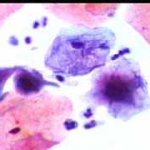

Papanicolaou: Πλακώδη επιθηλιακά κύτταρα κυρίως της επιφανειακήςστιβάδας, περίπου κατά50% και πλέον οξεόφιλα (16η ημέρα κύκλου!) . Ωστόσσο και αρκετά της διαμέσου και της παραβασικής, εν μέρει με διογκωμένους, ανισομεγέθειςαρραιοχρωματικούςδιαυγείςπυρήνεςKοιλοκυττάρωση.Η εικόνα συνηγορεί για δυσπλασία σοβαρού βαθμού.

Λόγω και του κολποσκοπικούευρήματος, μικροβιοψία που κατεδειξε ιστολογικώς CIN III